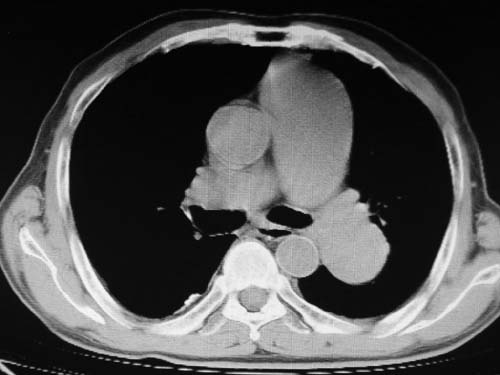

男,80岁

左肺动脉异常增粗,建议增强。

肺动脉瘤。建议先行ct增强扫描

左肺动脉异常增粗,考虑肺动脉狭窄可能。

1)考虑左肺动脉瘤可能性大,建议增强。2)右肺上叶继发性肺结核。3)右侧胸膜增厚、钙化,左侧胸膜反应。

肺动脉段突出,左右肺门不等大,左肺门明显增大,肺动脉干及左肺动脉明显增宽,考虑先天性肺动脉狭窄瓣膜狭窄型。

)考虑肺动脉扩张,右心室增大,主动脉弓段正常位弓后段明显变小(不会是动脉导客未闭吧,不知患者有何症状病史)0。2)右肺上叶继发性肺结核。3)右侧胸膜增厚、钙化,左侧胸膜反应。

肺动脉高压,左肺动脉瘤样扩张。